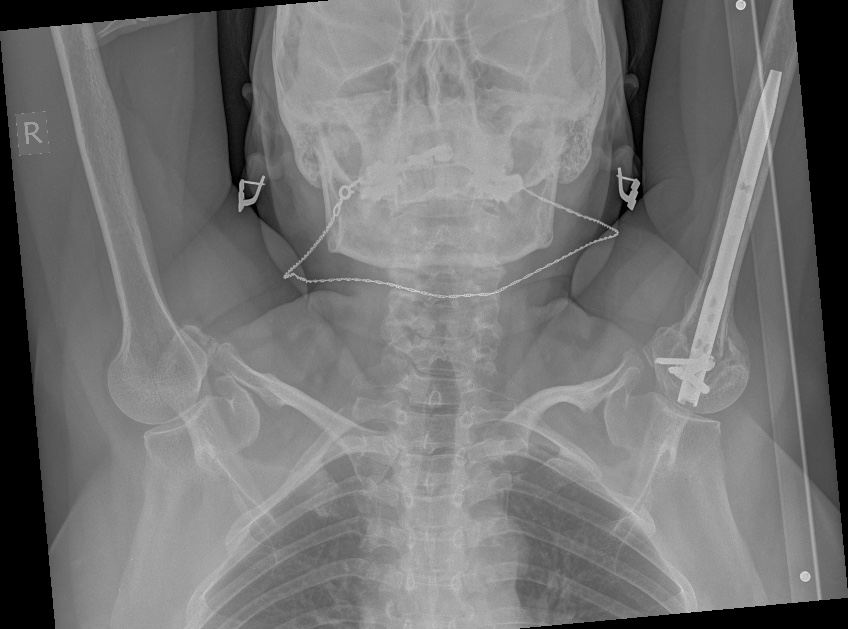

Нормальная тут головка. И есть уже не только Philos, но и Multiloc можно

закрыто. Или другой хороший PHN. И можно махать руками со следующего

дня. Вот результат как раз в похожей ситуации, двухмесячной давности

перелом.